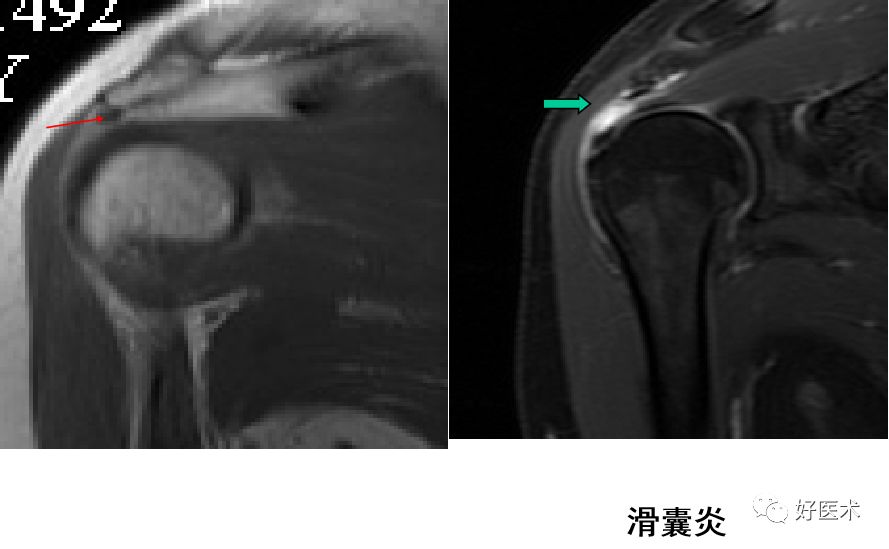

肩峰撞击综合征MR表现

肩峰下滑囊炎

-

T1WI-滑膜囊增厚呈低信号,高信号脂肪层消失;

T2WI-滑膜增生、炎症渗出呈高信号